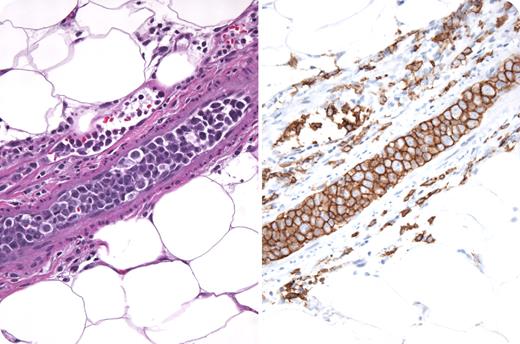

A 74-year-old woman presented with 6 months of fatigue, fevers, chills, dyspnea, weight loss, and blurry vision. Physical examination revealed only fever and mild splenomegaly. She had mild anemia, thrombocytopenia, lactic dehydrogenase that was 3 times normal, a markedly increased sedimentation rate, and hypoalbuminemia. CT/MRI of the head and body revealed no additional abnormalities. Bone marrow examination demonstrated moderate fibrosis, normal cytogenetics, and no dysplasia. She developed new skin nodules and a biopsy was performed. The photograph shows intravascular “plugs” composed of large atypical CD20 B cells with aberrant expression of CD5. Diagnosed as intravascular lymphoma (IVL), she received chemotherapy with rituximab (EPOCH-R) that resulted in a complete resolution of symptoms and disappearance of the skin nodules. IVL are rare, aggressive extranodal diffuse large cell lymphomas, characterized by intravascular malignant lymphoid tumor cells with a remarkable sparing of lymph nodes and nonvascular organ parenchyma. IVL are generally positive for CD19, CD20, CD22, CD79a, and occasionally CD5. Certain tumor cell surface molecules, such as CD11a/49d, may bind to CD 54/106 on endothelial cells and result in vascular compartmentalization. Clinical presentation is diagnostically challenging and nonspecific; nearly half of cases present with fever of unknown origin. Anemia, high lactic acid dehydrogenase levels, and high sedimentation rates are typical. CNS manifestations are also common and often fatal. More than half of cases are diagnosed postmortem; therefore, a high index of clinical suspicion is paramount. Median survival is 5.5 months; however, anthracycline-based regimens in combination with rituximab have proven successful. CNS-directed therapy is recommended for patients with neurologic symptoms.